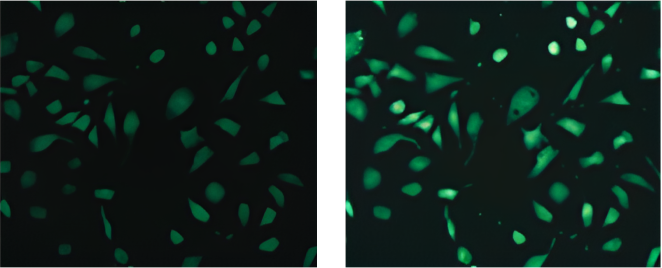

Left: Before incubation. Right: After stimulation. Image Credit: Yokogawa Life Science

An integrated robotic pipette with disposable tips enables drug addition during imaging, making it ideal for high-speed phenomenon monitoring in kinetic experiments.